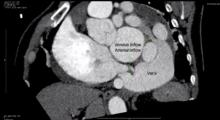

This video depicts the surgical correction of a complex congenital arterial venous coronary fistula in a 49-year-old male patient, who presented with a three-day history of palpitations and a continuous murmur. Subsequent investigations demonstrated a complex fistula between the right coronary artery, the mid circumflex, and the coronary sinus resulting in a venous aneurysm. The anatomy of the fistula precluded transcatheter closure, therefore the patient was listed for surgery. The surgery was performed on cardiopulmonary bypass. It entailed excision of the venous aneurysm, and closure of the fistulous communications using bovine pericardial patches. One year after the procedure, the patient has remained asymptomatic and has resumed exercising. His follow-up CT angiogram demonstrated a very small persistent fistula of no clinical significance that does not require further intervention.